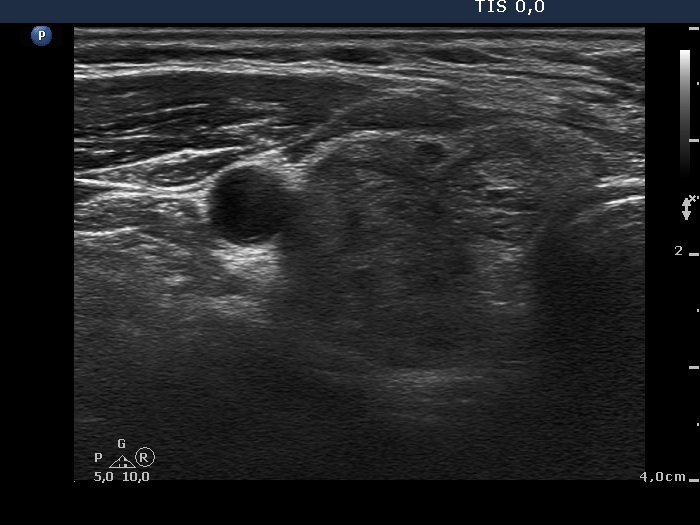

Patient referred for evaluation of thyroid nodule - final diagnosis Hashimoto's thyroiditis - Case 14. (ultrasonographic picture 2)

Lowr part of the right lobe, horizontal view.